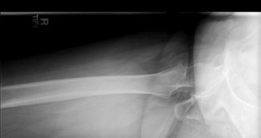

Standard antero-posterior and cross-table lateral radiographs of the pelvis and left hip were obtained immediately following the primary clinical assessment.

The initial AP pelvis radiograph clearly demonstrated a displaced left femoral neck fracture. The fracture line was entirely intracapsular. The femoral head was superiorly and posteriorly displaced relative to the femoral neck, with evidence of approximately 1.5 cm of shortening. The bone quality appeared reasonable for the patient's age, with a preserved Singh index and cortical thickness in the diaphyseal region, though some osteopenia was evident in the proximal trabecular patterns. No signs of pre-existing significant hip osteoarthritis (such as joint space narrowing, subchondral sclerosis, or osteophytosis) in the ipsilateral joint were noted. The contralateral hip appeared unremarkable.

Further radiographic views confirmed the complete displacement and the lack of cortical contact between the proximal and distal fragments. The fracture was classified as a Garden Type IV, indicating complete displacement with a loss of trabecular alignment between the femoral head and the acetabulum, where the head has rotated independently of the neck. Furthermore, it was classified as a Pauwels Type III, meaning the fracture line angle was greater than 70 degrees from the horizontal. This vertical fracture orientation indicates extremely high shear forces across the fracture site, portending a very poor prognosis for osteosynthesis and a high risk of nonunion or fixation failure if internal fixation were to be attempted.